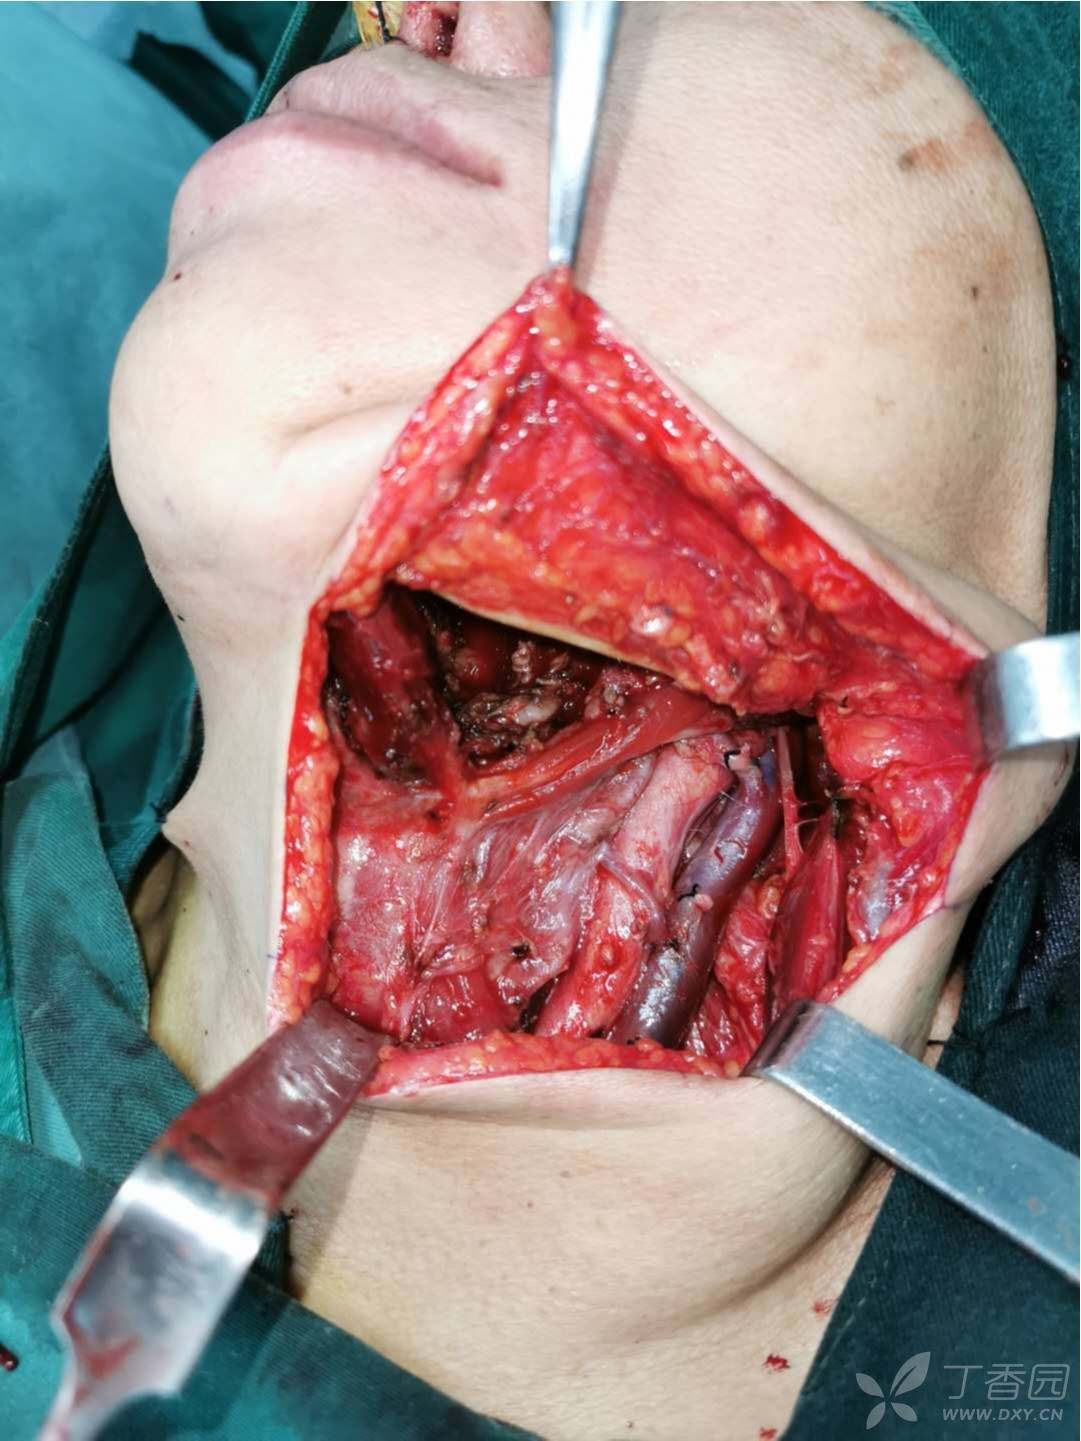

舌癌扩大切除 前臂皮瓣修复(游离皮瓣修复)

舌癌根治术同期行前臂皮瓣舌再造

聚焦医疗技术近日我科成功开展舌癌扩大切除术

眉山市中医医院耳鼻咽喉头颈外科成功实施一例舌癌扩大切除 舌体重建